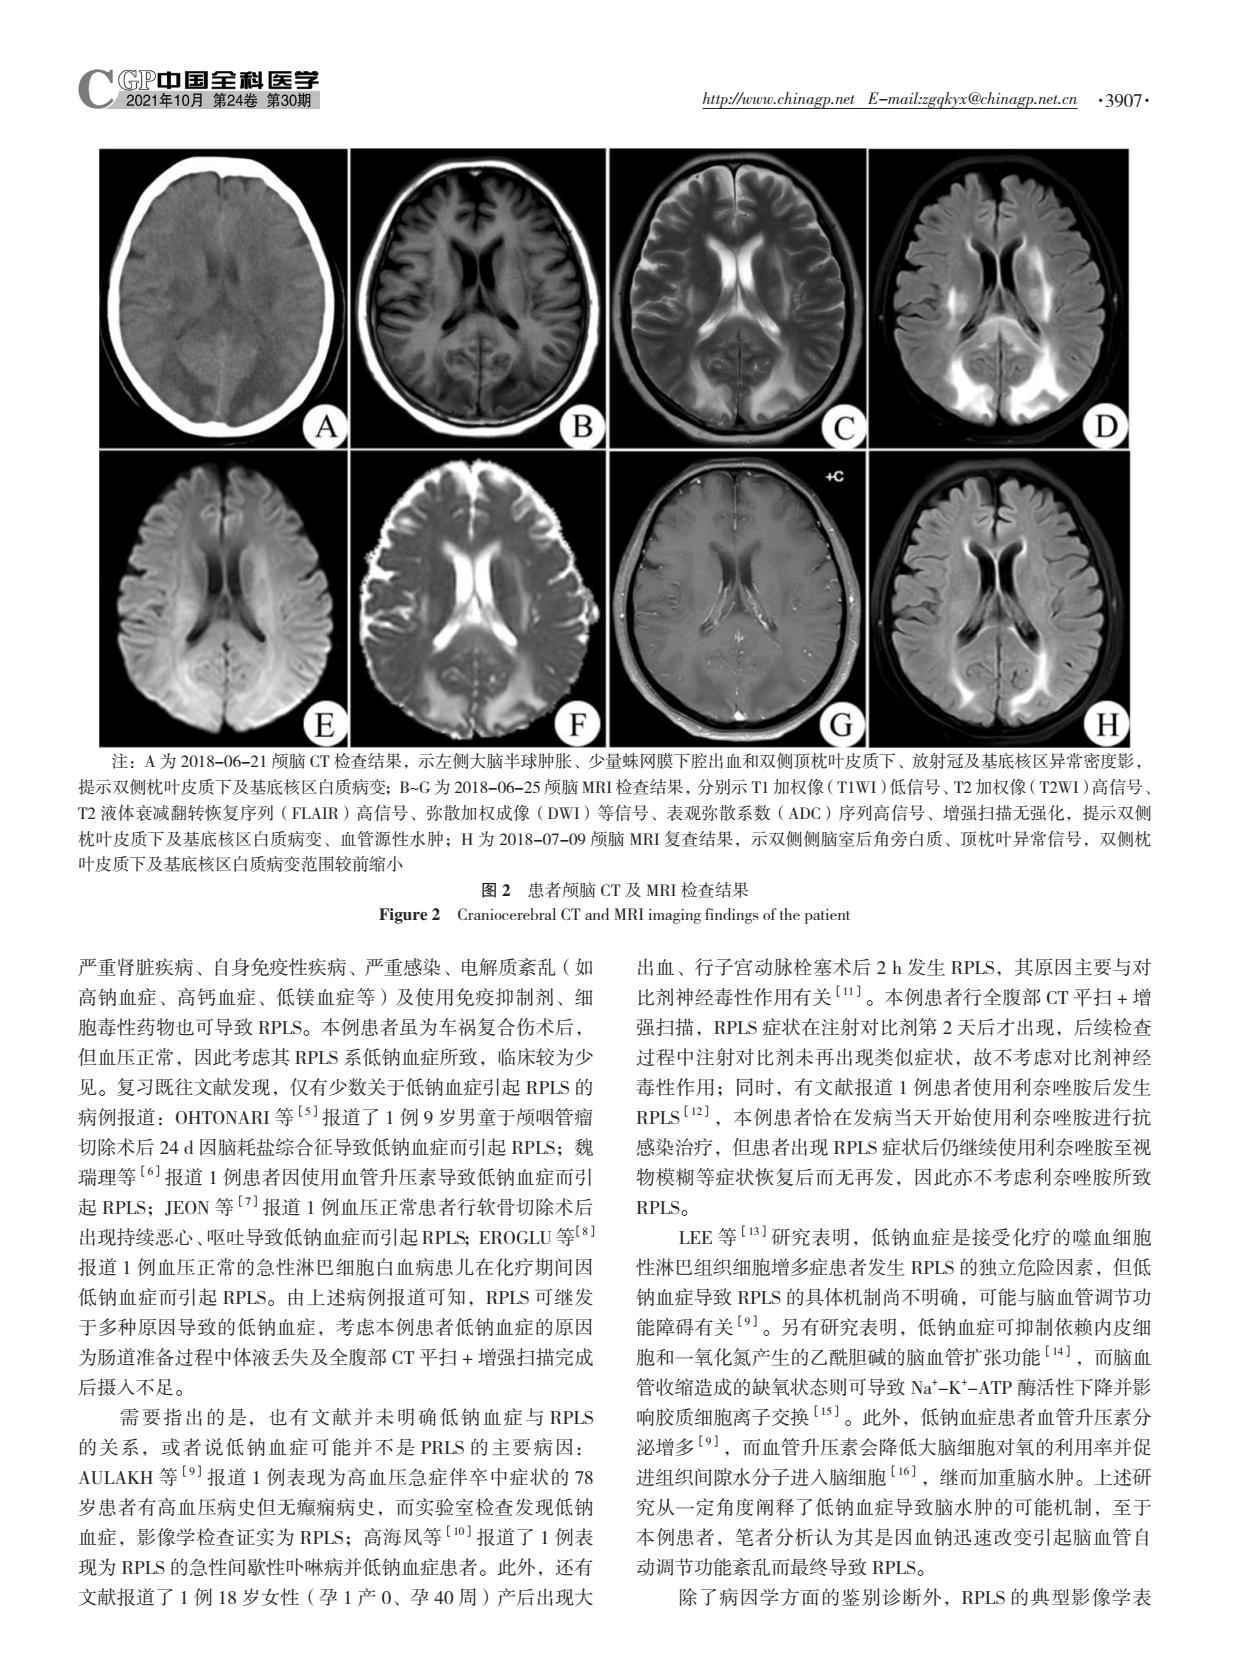

【 摘要 】 可逆性后部白质脑病综合征(RPLS)是一组临床少见的急性或亚急性起病的神经影像学综合征,主要临床表现包括头痛、头晕、恶心、呕吐、癫痫发作、视觉障碍、意识障碍及精神行为异常等,典型影像学表现为可逆的对称性大脑后部白质病变。本文报道了1例车祸复合伤并低钠血症所致RPLS患者,并进行了文献复习,提示低钠血症是导致RPLS的少见原因。临床上遇到各种原因导致的低钠血症患者时应警惕RPLS的发生,而RPLS通常是可逆的,早期识别和治疗对防止永久性神经系统后遗症的发生至关重要。